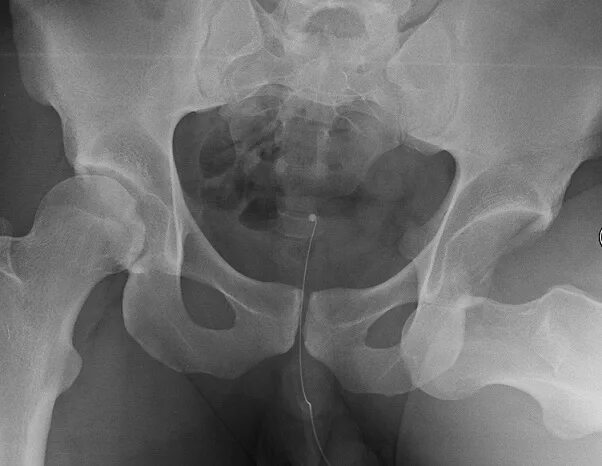

Операция тазобедренного сустава у взрослых